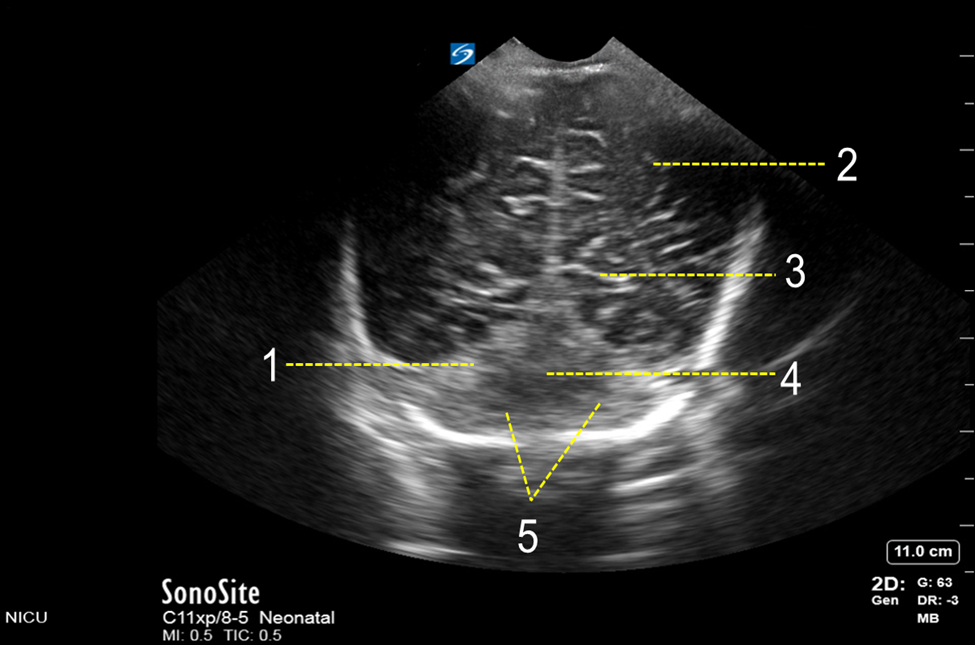

Neonatology Posterior Fontanelle Inferior Coronal View Image

1. Tentorial Area

2. Occipital Lobe

3. Calcarine Fissure

4. Cerebellar Vermis

5. Cerebellar Hemisphere